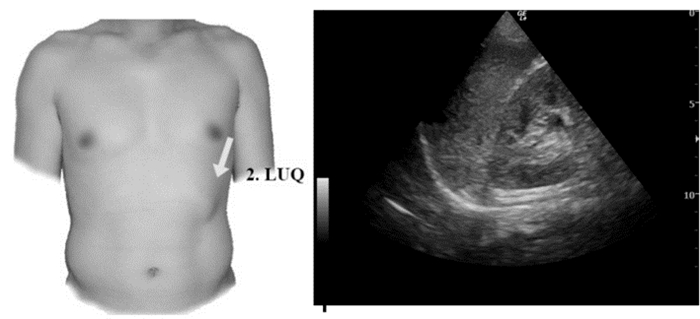

3.1.3 创伤的超声诊断的步骤及流程(1)创伤的超声诊断步骤:创伤患者床旁超声检查至少5个部位:①右上腹,也叫肝周切面、莫里森窝切面或右上1/4切面。如出现无回声区提示腹腔内出血(图 22-23)。②左上腹脾肾间隙,如出现无回声区亦提示腹腔内出血(图 24-25);③耻骨上/盆腔切面,如显示膀胱后或子宫后无回声区,提示盆腔出血可能(图 26-27);④剑突下切面,常用于探查心包有无无回声区(图 28),具体心包积液征象见2.1.2 常见异常超声心动声像图。⑤肺部超声,主要用于探查有无血气胸、肋骨骨折,具体征象见2.2肺超声。

| 图 24 脾肾间隙部位及正常超声影像 |